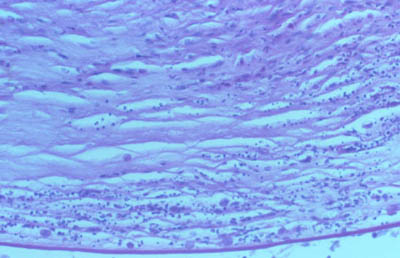

A - CW B - Giemsa C - PAS D - Gram

Tejido corneal Procesado

H&E

PAS

CW

PAS